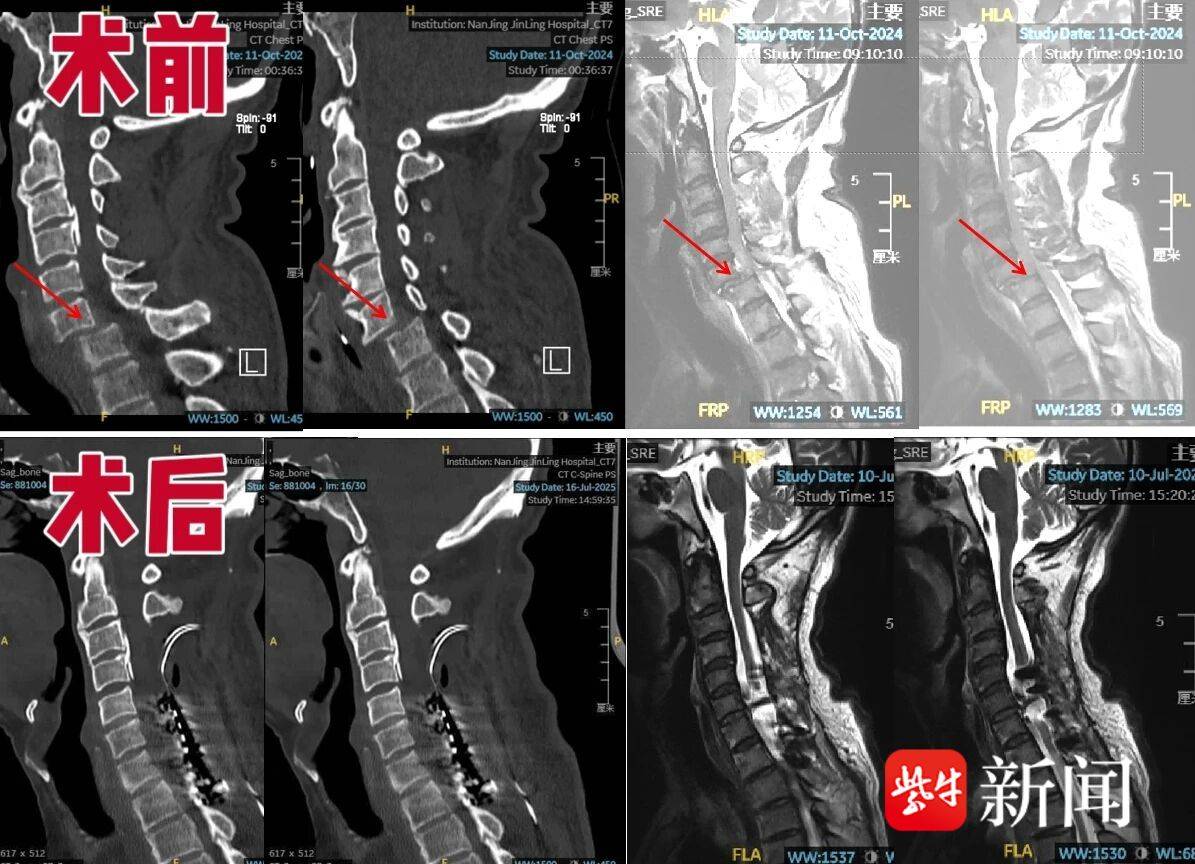

患者曾先生一年前因高处坠落致颈椎脱位,引发颈髓严重损伤,造成双下肢运动与感觉功能丧失,并继发顽固性低血压。虽经手术复位,保住了生命,但曾先生低血压一直无法纠正,每日需服用大量升压药,血压仍只能维持在66/40mmHg左右的低水平状态,常感到头晕心慌、视物模糊,甚至有濒死感,导致术后9个月都无法开展康复治疗。

经安放临时电极刺激有效后,7月28日,团队为曾先生进行了永久脊髓电极植入。术后,患者血压很快恢复正常,完全停用所有升压药物。令人欣喜的是,术后,患者双上肢肌力由3级恢复至4级,双下肢肌力也由0级提升至1级,其神经功能也出现了积极变化,为后续系统康复创造了有利条件。